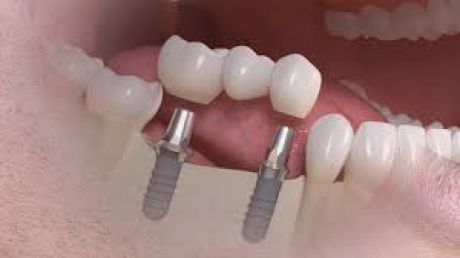

Implants have established themselves as the most durabledental prosthesis - they help not only to create a beautiful smile and aesthetics but also to improve the quality of life. An implant takes the function of a tooth root and forms the pillar for the dentures. It is invisible in the jaw and firmly anchored. For the implants only pure titan material is used, since this material has a high body tolerance and no allergies are known. One of the greatest advantages is that the healthy teeth don't need to be grinded down to fix a bridge or a removable prosthesis. With implants the patient doesn't feel any difference to his natural teeth.

Dental implants are as close to the original condition as no other restoration. The new tooth roots inteosseograte after implantation. The implanted screw serves as the foundation for single tooth crowns or bridges. Prostheses can also be securely fixed using implants. They do not have any restrictions in everyday life, such as laughing, talking or chewing.